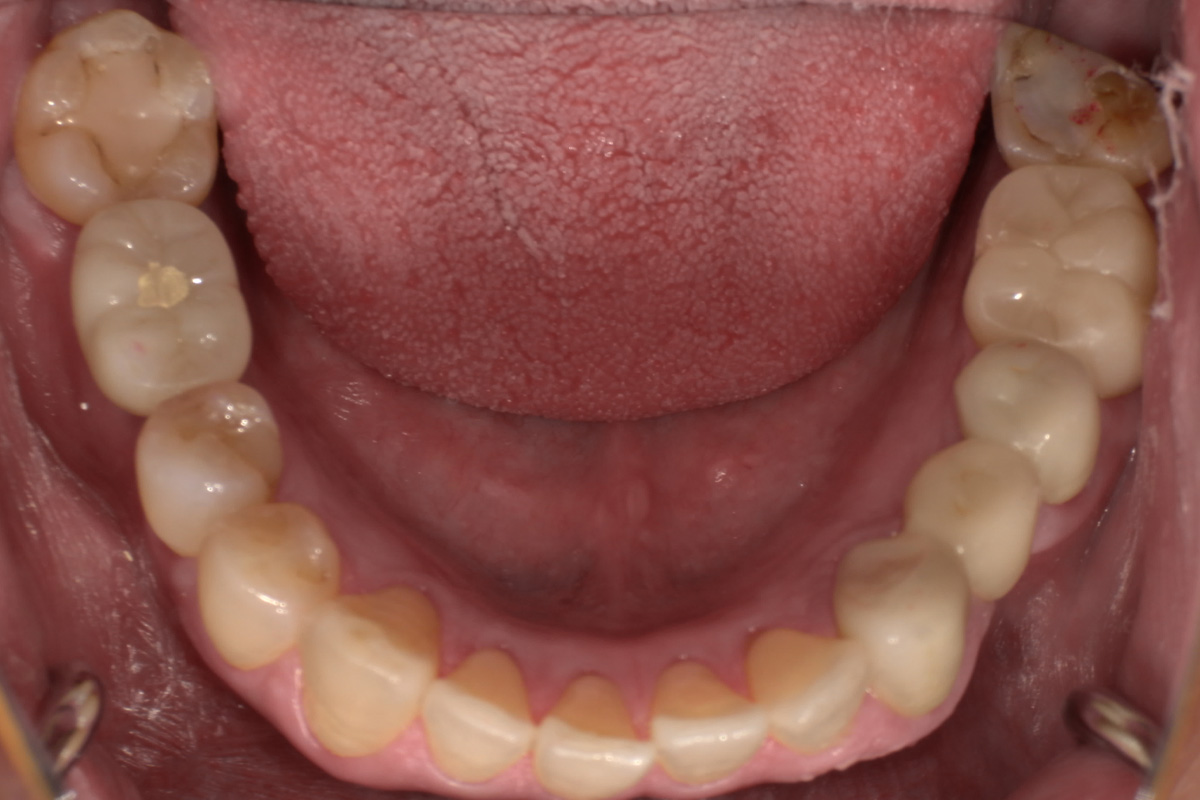

初診時

歯が割れていて、痛みがあり、抜歯となりました。

パノラマレントゲン写真 -

親抜歯後、歯ぐきは治癒しました。しかし、インプラント治療のためには骨が不足していました。

CT画像 -

骨移植(人工骨+メッシュプレート)を行い、骨を造りました。

インプラント手術を行いました。

インプラント手術から3ヵ月後、型どりをして、仮歯を製作しました。

仮歯の調整期間を経て、セラミックの歯が入りました。

レントゲン画像 治療前 インプラント治療後